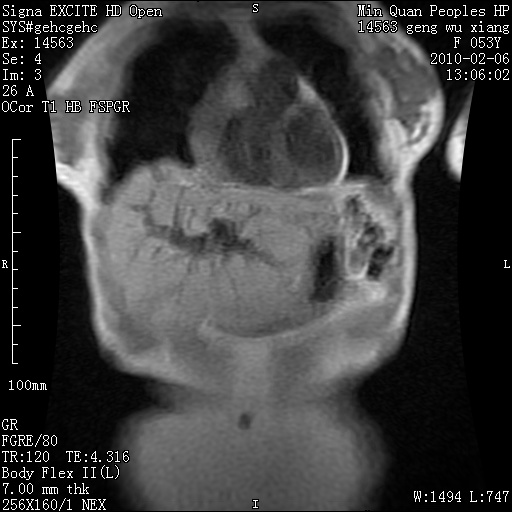

标题: MRI2762:胆道梗阻原因?

f,53y,全身黄染多日。

高位胆道梗阻 胆管癌可能性大

支持 高位胆道梗阻 胆管癌可能性大。